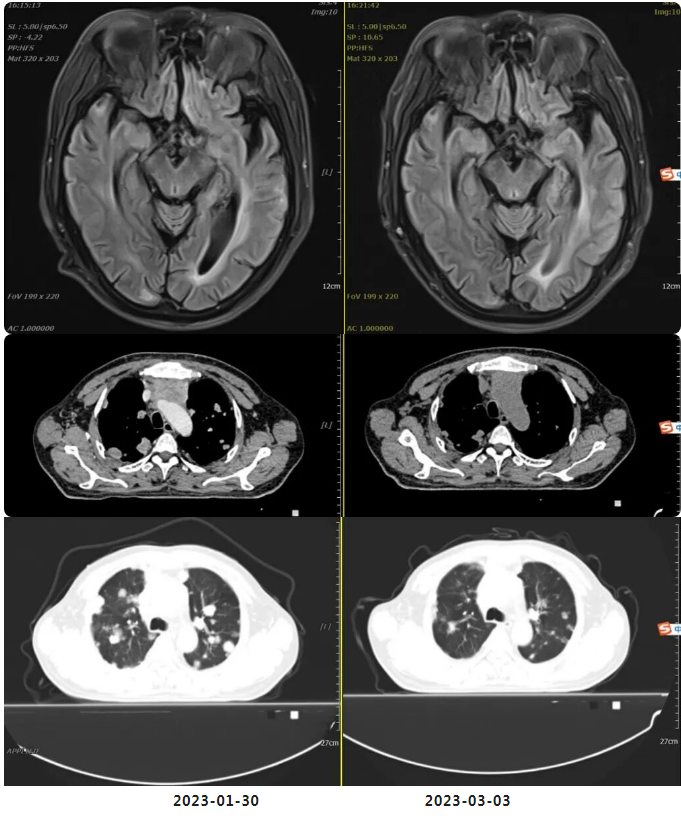

2023年1月30日开始口服“马来酸阿法替尼片(自带)40mg 口服 qd”靶向治疗。

2023年3月3日我院复查胸腹盆平扫CT、头颅平扫MR:疗效评估:SD(病情稳定)